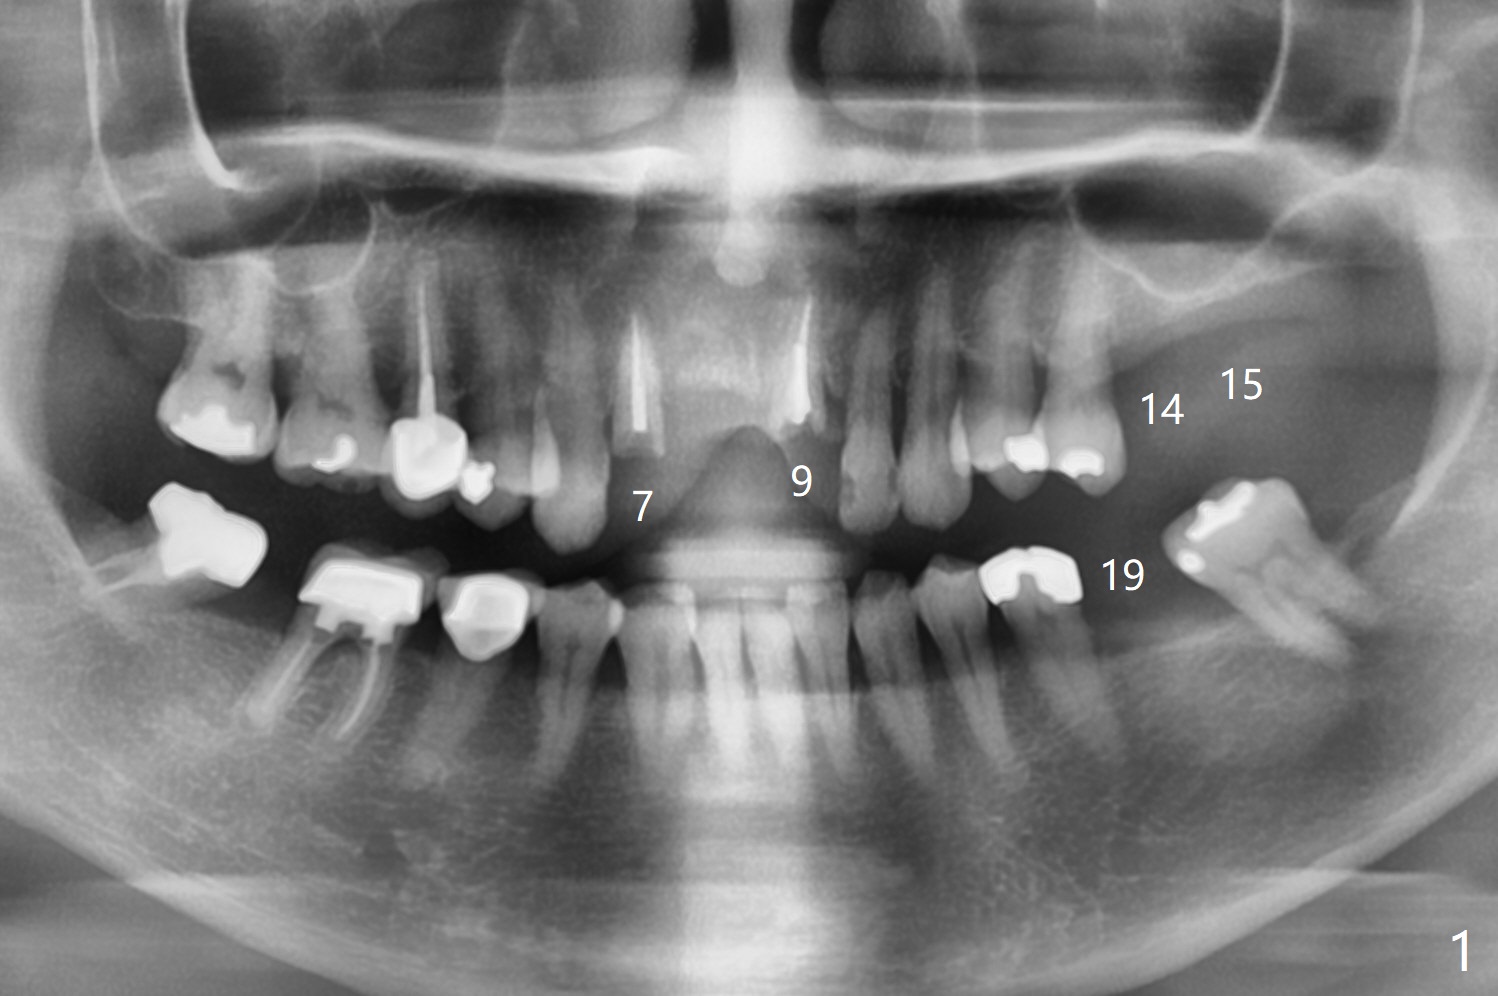

A 56-year-old woman without much posterior support has fractured #7-9 FPD (Fig.1). Since the bone at #7 is thinner buccopalatal than that of #9 (compare Fig.2,3), a shorter implant will be placed at #7 with an angled abutment. External sinus lift is required with PRFx2 before implantation at #14 and 15 (Fig.4). For #19 with the narrow mesiodistal space, a narrow implant is indicated (Fig.5).